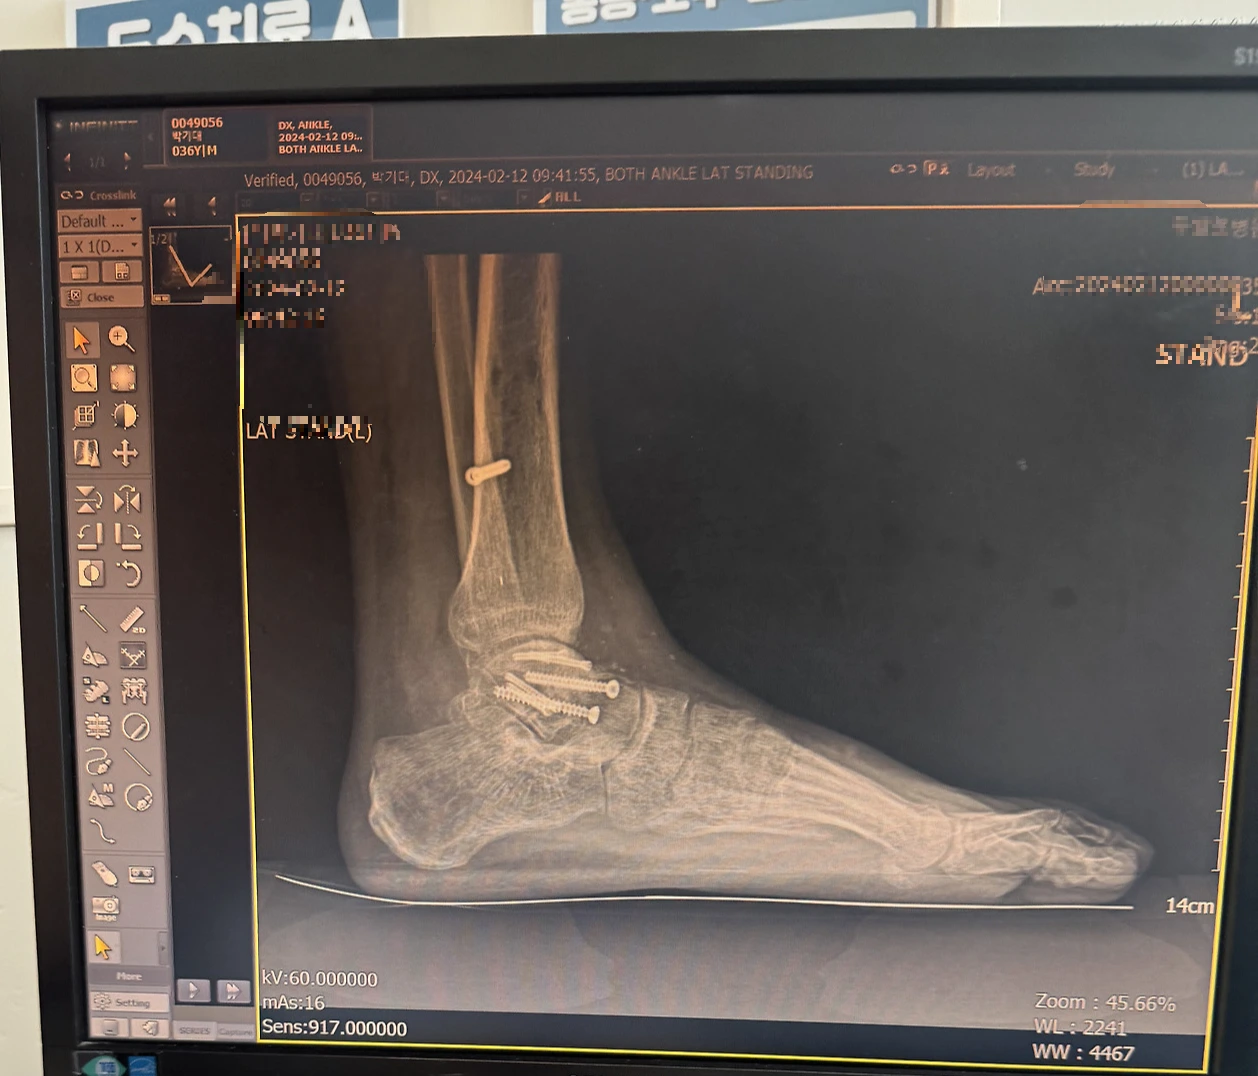

아침에 일어나면 발목은 더욱 굳어 있었다. 자는 동안 움직이지 않았기 때문이다. 발목이 굳는 현상은 20~30분 정도 그냥 않아 있어도 나타났다. 움직이지 않고 있으면 굳는 것이었다. 특히 발목이 굳을 때 45도로 굳기 때문에 발로 지면을 수직으로 디딜 수 없어 절뚝거릴 수밖에 없었다. 굳은 상태에서 계속 걸으면 굳은 상태가 풀어서 똑바로 걷기는 했지만 시간이 좀 걸렸다. 발목에 핀이 6개나 박혀있어서 그런지 이물감도 있었다. 부종은 덤이었다.

거골과 정강이 뼈사이 앞쪽 뼈가 자라 있다.

발목 상태는 확실히 예전보다 많이 좋아지고 있었다. 하지만 원래 상태로 돌아가기는 힘들 것 같다는 생각 때문에 좌절하기도 했다. 정기적으로 병원에 방문해 수술한 발목에 이상이 있는지 검사를 하였다. 병원에 방문할 때마다 x-ray와 CT 촬영을 했다. 어느 날 의사 선생님이 정강이 뼈과 거골사이에 뼈가 자랐다는 것을 발견하였다. 사고 날 때 정강이 뼈가 거골에 세게 부딪쳐 거골이 두 동강으로 분쇄 골절이 났다. 이 두동강으로 부러진 부분이 발목 앞쪽이고 이곳의 연골이 많이 손상되었다. 그리고 회복 중 그곳에 뾰족한 뼈가 자라났다. 의사 선생님은 자라난 뼈가 연골을 긁을 것을 걱정하셔서 발목을 앞으로 굽히지 말고 뒤쪽으로만 굽히는 연습을 하라고 하셨다. 그리고 뛰지 말고 자전거만 타라고 하셨다. 회복이 잘되고 있는 줄 알았는데 뜻밖의 상황이 벌어졌다. 평생 못 뛸 수도 있다는 생각에 걱정이 많아졌다.